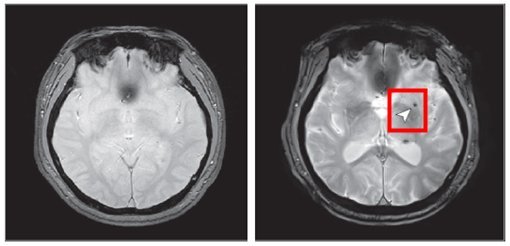

후 뇌 미세출혈이 발생한 뇌영상 이미지

뇌 미세출혈은 뇌 속의 작은 혈관이 손상되어 출혈이 발생하는 것으로, 뇌졸중 등 심각한 뇌혈관 질환의 주요 위험요인으로 알려져 있다.